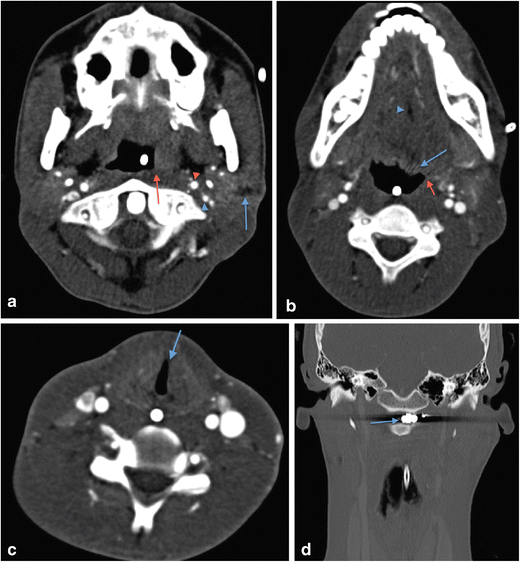

a Axial non-contrast CT face image in a 19-year-old male victim of a shotgun injury to the orbito-facial region. Multiple shotgun pellets are identified in the malar soft tissues, nasal fossae, maxillary sinuses, nasopharynx and masticator space, particularly on the right at this axial level. Fracture fragmentation of the right maxillary sinus, malar and retroantral haematoma and antral haemorrhagic fluid are present. The involvement of the nasal, nasopharyngeal and oral (the latter not shown) airway raises potential for distal migration of pellets (as well as of in-driven tissue fragments) through the upper aerodigestive tract into the lower respiratory tract and gastrointestinal tract. b Plain chest radiograph in the same patient as in 13a performed during trauma survey on admission demonstrates distal migration of a shotgun pellet (blue arrow) into the mid-oesophagus (confirmed on CT chest assessment [not shown]). The patient is intubated. c Axial image of a contrast-enhanced CT thorax of the same patient as in a and b, performed 12 h later also confirms aspiration of a shotgun pellet (blue arrow) associated with distal subsegmental left lower lobe atelectasis (blue arrowhead). There had also been further distal intra-oesophageal migration of the mid-oesophageal shotgun pellet (image not shown)